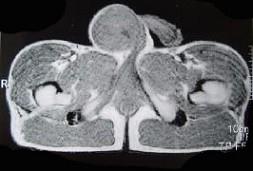

问题 29岁男性患者,右侧睾丸肿痛5个多月,行MRI检查,如图所示,T1加权见右侧阴囊内见球形肿块,呈中等信号,其内信号不均,T2加权肿块为高信号,最可能的结果是 ( )

选项 A、皮样囊肿 B、畸胎癌 C、睾丸结核 D、畸胎瘤 E、精原细胞瘤

答案 E